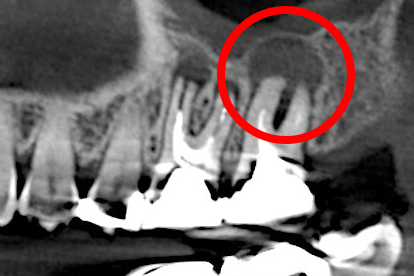

他院で根管治療を受けたが痛みが取れず、当院で歯根端切除を行った。

術後8カ月、きれいに骨が再生している。

• 治療前

• 治療後

他院で根管治療を行ったが治癒せず、当院で歯根端切除を行いMTAセメントを充塡した。

術後8年後の様子。骨はきれいに再生している。

歯の根の炎症を治療する「歯根端切除術」

歯の根の先に炎症が発生し、膿が溜まった場合、最悪の場合、抜歯を勧められることがあります。しかし、私たちでは「歯根端切除術」を用いて、歯を抜かずに処置することが可能なケースもあります。

歯根端切除術とは、歯茎の外側を外科的に切開し、炎症を起こしている歯の根の先端と膿を含む袋を一緒に取り除く手法です。手術後の空間は血液で満たされ、やがて自然に新しい骨が再生し、空洞を埋めていきます。

歯根端切除術は、簡単な治療ではありません。歯根端切除術を得意としている医院でも、奥歯にはできないことが多いのですが、当院は、奥歯であっても対応が可能です。